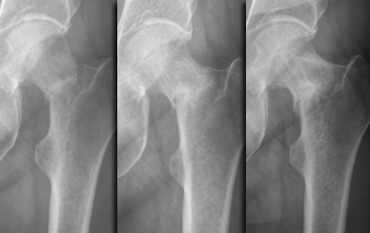

Follow-up radiographs at 1, 3 and 13 months Follow-up radiographs at 1, 3 and 13 months

A radiograph made one month later shows evolvement to complete fracture.

Although this is a low-risk fracture, the follow-up radiographs at 3 and 13 months did show poor healing tendency.